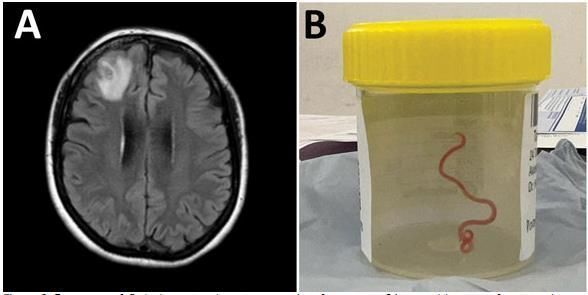

이에 따라 캔버라의 한 병원에서 MRI로 확인한 결과 수술을 해야 한다는 소견이 나왔고 이 여성을 집도하던 하리 프리야 반디 신경외과 의사는 수술 도중 아주 충격적인 상황을 맏닥뜨려야 했습니다.

이 여성의 뇌에는 비단뱀에서 볼 수 있는 회충의 종류로 '오피다스카리스 로베르시'라는 벌레가 있었으며 문제는 이 회충이 살아서 꿈틀 거렸다고 하였습니다.

이렇게 사람의 몸에서 발견된 것은 처음이며, 회충의 길이는 8Cm정도의 길이로 생각만 해도 끔찍한 모습이 아닐 수 없습니다.